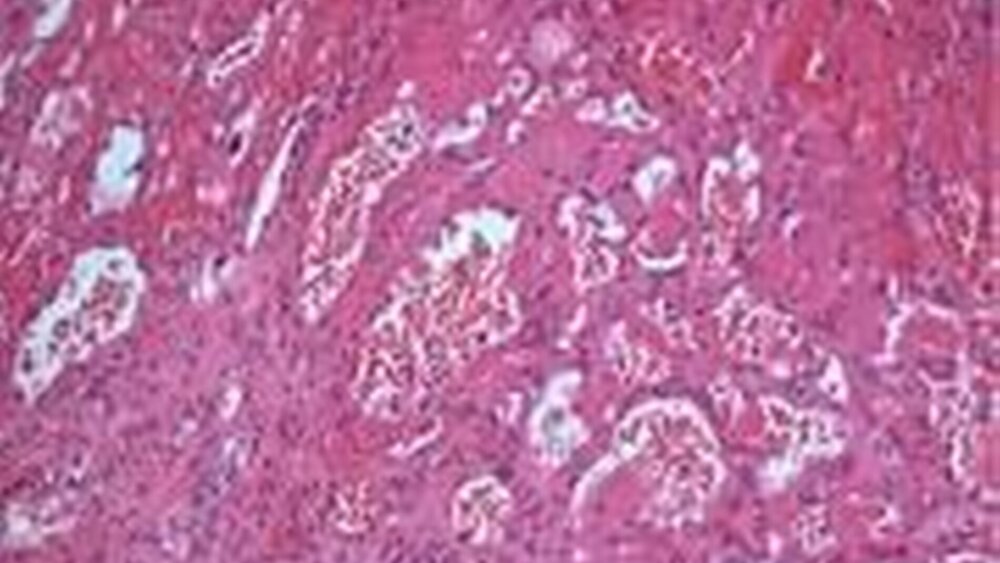

Histologisch zeigten sich in der HE-Färbung Konglomerate geweiteter Kapillarräume, umgeben von einem gemischtzelligen Entzündungsinfiltrat, das sich vornehmlich aus neutrophilen Granulozyten zusammensetzt (Abbildungen 4 a und b). Die histologischen Präparate wurden freundlicherweise von Dr. Wiltrud Coerdt, Institut für Kinderpathologie der Johannes Gutenberg-Universität Mainz, zur Verfügung gestellt. Die Übersichtsvergrößerung (4 a) zeigt die Randzone, in der die Epithelbedeckung der umgebenden Schleimhaut abbricht. In der Detailaufnahme (4 b) wird die dichte Anordnung sinusoidaler Bluträume mit endothelialer Auskleidung sowie die Füllung mit Erythrozyten deutlich. Es finden sich keine zellulären Atypien. Diese Morphologie ist typisch für ein eruptives Angiom.